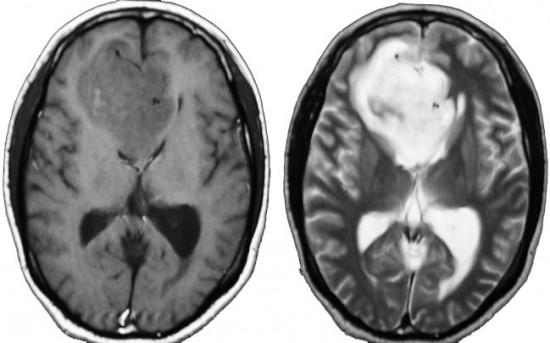

症候性てんかんのみで発症した右側頭葉と島回のグレード2オリゴです。左のT2,中央のフレアではグレード2びまん性星細胞腫と鑑別はできません。認知機能などは正常でした。

何と言っても診断的価値があるのは 石灰化 carcification です。左のCTの中央にみえる白い部分が石灰化です。この程度の石灰化でも診断的な価値があります。1p/19q codeletionがあるオリゴでした。病理では,均一な小型の円形核を有する細胞と多数の毛細血管 chickin-wire network がみられます。部分摘出後,放射線治療とテモゾロマイド化学療法でコントロールできています。